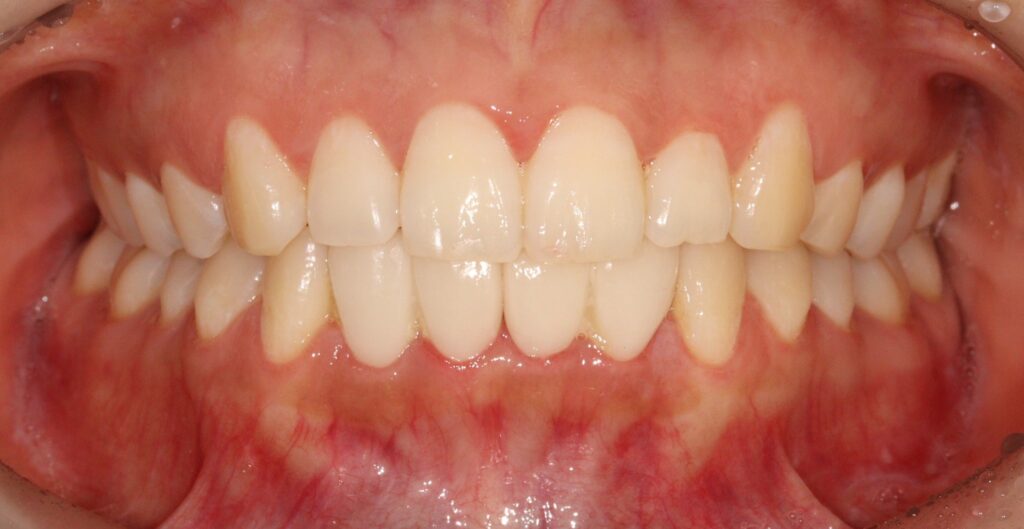

잇몸치료 후 회복시간을 두고 PMMA 프로비저널 크라운으로

환자분의 심미적 요구도를 확인해서

최종보철에 반영하였는데요.

빠르게 문제 없이 최종 보철까지 마무리 되어

환자분께서도 매우 만족하셨습니다.